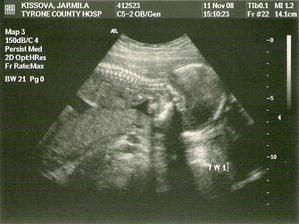

jarka82

16. nov 2008

Moje druhe tehotenstvo

Toto su moje prve ultrazvuky cakame jednovajecne dvojicky a pohlavie zatial nevieme